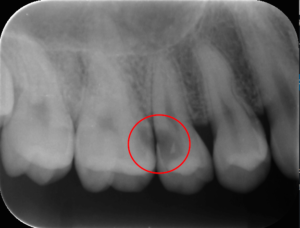

しかし直接見ることができない歯と歯の間などは、

レントゲンを撮影してみつけることが多い虫歯です。

上の画像の赤い丸の部分が虫歯です。この虫歯は口の中を直接見るだけではみつかりません。